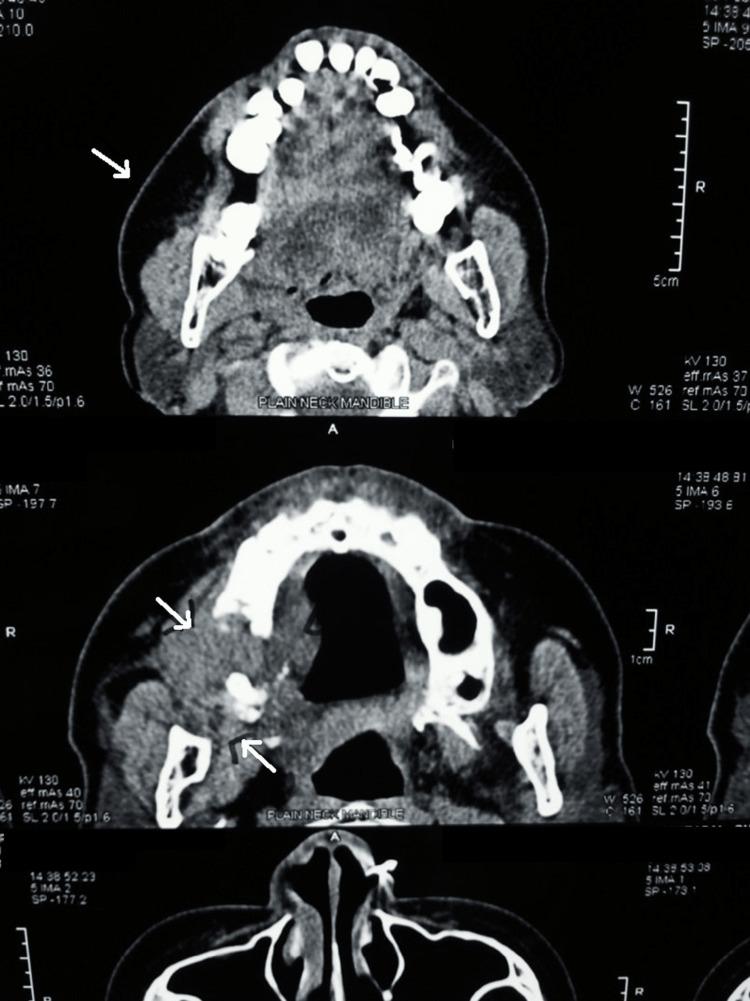

Melanoma of the oral cavity is a rare malignant tumor that develops from a malignant melanocytic or de novo from melanocytes within the normal mucosa or skin and appears blue, black, or reddish-brown. Oral mucosal melanoma has a higher proclivity for metastasis and attacks tissue more aggressively than any other malignant tumor in the mouth. Intestinal melanoma of the head and neck is an uncommon type of cancer that should be counted among the deadliest. Malignant melanoma of the oral cavity accounts for only 0.2%-8.0% of all reported melanoma, although accounting for 1.3% of all malignancies. Because most melanotic mucosal lesions are painless at first, the diagnosis is sometimes delayed until the ulcer or growth causes symptoms. Early detection is critical for effective therapy and the only way to improve survival and prognosis in patients with oral malignant melanoma due to its poor prognosis. To avoid oral melanomas, every single colored lesion identified in the oral cavity should be treated with suspicion and adequate inquiry because a colored lesion might expand, and it should be referred for a biopsy to avoid poisoning. This article shows how the oral clinic is important in the diagnosis of oral ulcers and argues that early detection is necessary to enhance patient outcomes.

口腔黑色素瘤是一种罕见的恶性肿瘤,它由恶性黑素细胞发展而来,或者起源于正常黏膜或皮肤内的黑素细胞,表现为蓝色、黑色或红棕色。口腔黏膜黑色素瘤比口腔内的任何其他恶性肿瘤更易发生转移,侵袭组织的能力更强。头颈部肠道黑色素瘤是一种罕见的癌症类型,属于最致命的癌症之一。口腔恶性黑色素瘤仅占所有报告黑色素瘤的0.2%-8.0%,尽管占所有恶性肿瘤的1.3%。由于大多数黑色素性黏膜病变起初无痛,诊断有时会延迟,直到溃疡或肿物引起症状。早期检测对于有效治疗至关重要,由于口腔恶性黑色素瘤预后较差,这也是改善患者生存和预后的唯一途径。为避免口腔黑色素瘤,口腔内发现的每一个有色病变都应受到怀疑并进行充分询问,因为有色病变可能会扩大,应转诊进行活检以避免误诊。本文展示了口腔诊所在口腔溃疡诊断中的重要性,并认为早期检测对于改善患者预后是必要的。